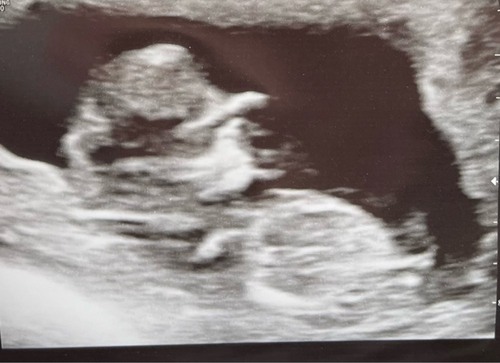

Wat denken jullie? 11+3 hier.

Wat denken jullie, 💖 of 💙 3 oktober uitgerekend

Ben benieuwd wat jullie denken 11.2 🥰

Net de termijn echo gehad, 11.4❤️.. wat denken jullie? 💞💙

Ik denk een meisje obv deze echo. Ben benieuwd!

Nog een poging wagen, ben benieuwd naar meer reacties. Zo nieuwsgierig! 😍